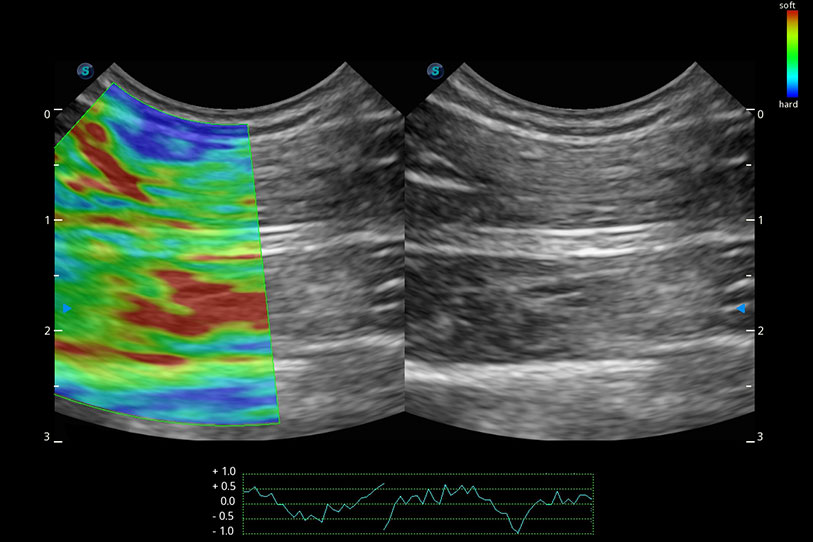

操作簡便,無需高頻度外力作用即可真實(shí)反映組織的形變,快速評估腫瘤良惡性。